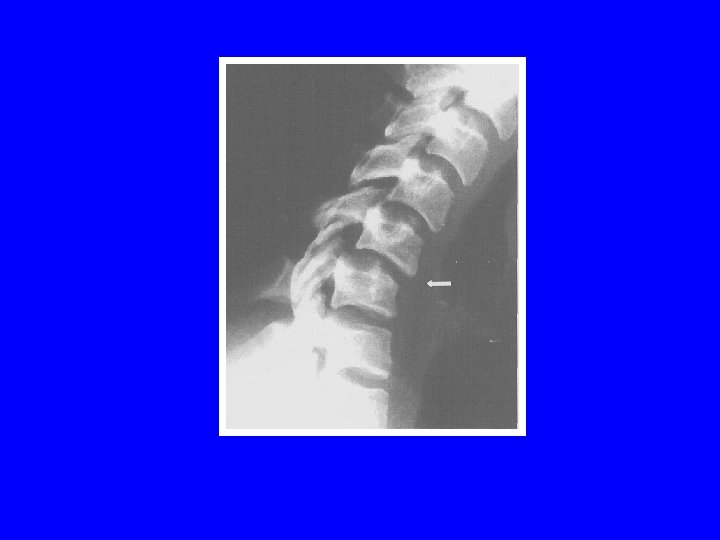

LESIONS MIXTES: LA FRACTURE TEAR DROP Schneider et Kahn (1956) Mécanisme en flexioncompression trait de fracture frontal trait de fracture sagittal trait de fracture lamaire lésions ligamentaires LLV, LLD, disque

Prédomine en C 5 (65%) Neuroagressivité++ stade 3 de Allen: 25% (médullaire) stade 5 de Allen: 91% (médullaire) Instabilité selon l ’atteinte discoligamentaire Les disques sus et sous-jacents peuvent être atteints Double tear drop

LESIONS MIXTES: LA FRACTURE TEAR DROP Allen (1986): 5 stades stade 1: aspect émoussé du coin antéro-inférieur stade 2: perte de hauteur partie antérieure du corps stade 3: trait de fracture en goutte d ’eau stade 4: stade 3+ déplacement postérieur <3 mm stade 5: stade 3+ déplacement postérieur >3 mm

Tear drop stade 3 Tear drop stade 4